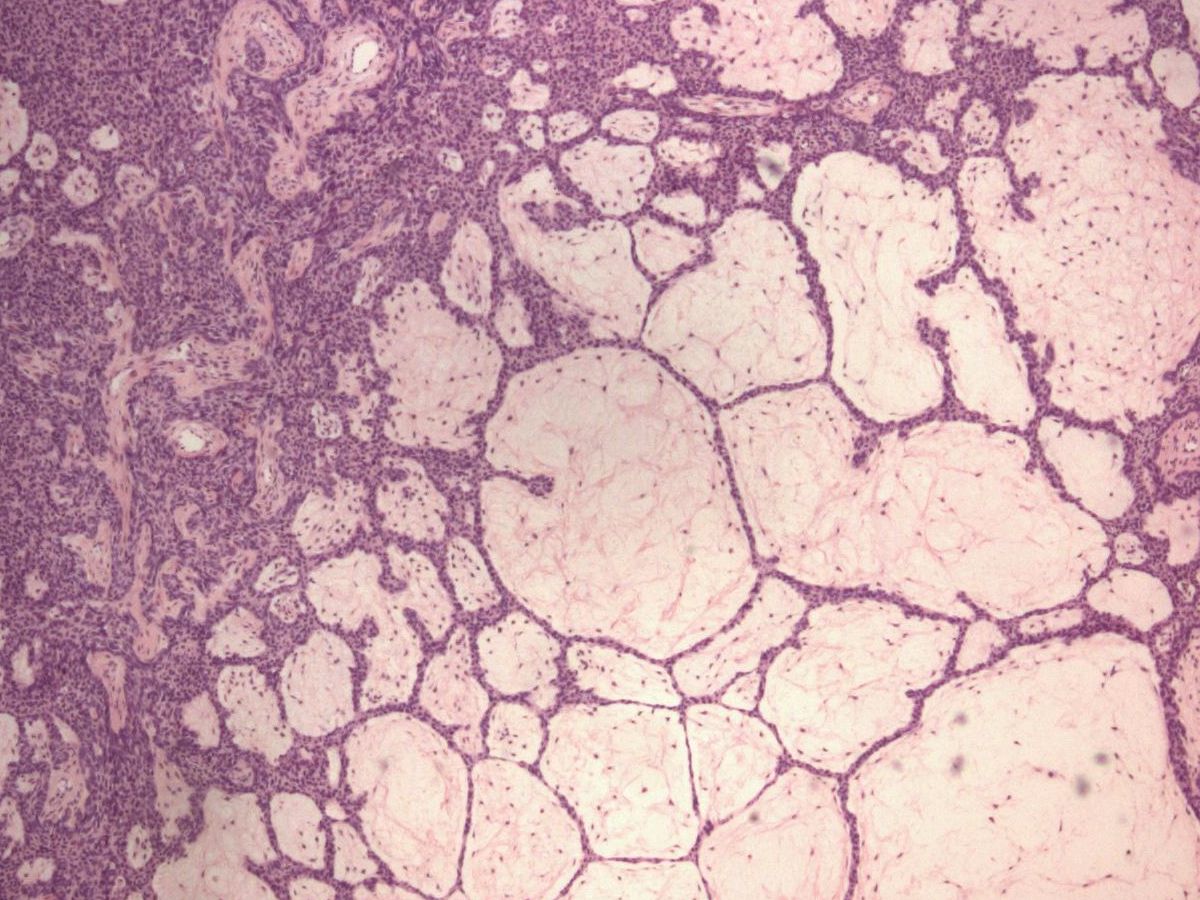

![Fibroepithelioma (Pinkus tumor) (click on photo to enlarge) [source: www.huidziekten.nl] Fibroepithelioma (Pinkus tumor)](../../../images/pinkus-tumor-2z.jpg) |

fibroepithelioma

(Pinkus) |

PA:

De histologie toont dunne anastomoserende strengen basaloide keratinocyten (soms

squameuze differentiatie) die ruimten gevuld met stroma omlijsten als 'kozijnen

rond een ruit'. Driedimensionaal gaat het om een honingraat vormige of sponsachtig

opgebouwde tumor die begint in de papillaire dermis en die bij groei de papillaire

dermis opblaast en een gesteelde laesie vormt. In de ruimten groeien soms structuren

die lijken op haarzakjes in vroege embryonale ontwikkeling, die 'follicular

germ-like structures' worden genoemd. Immunokleuringen tonen vaak (85%) cytokeratin

20 (CK20, Merkel cellen) en BCL-2 (proto-oncogen), soms androgeen receptoren,

soms zwakke aankleuring p53 of proliferatie marker Ki-67. Sommige pathologen

beschouwen het als een gefenestreerde variant van een trichoblastoom. Het niet-aggresieve

gedrag past daar goed bij. Cysteuze varianten komen voor.